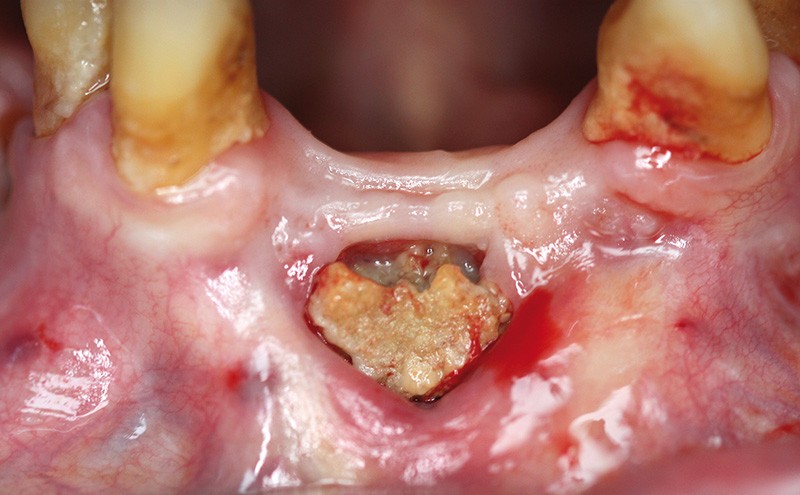

Une femme âgée de 82 ans est adressée pour une nécrose osseuse maxillaire postextractionnelle persistante (fig. 1). Elle se présente avec une oxygénothérapie liée à une insuffisance respiratoire chronique, consécutive, à une thrombophlébite avec embolie pulmonaire.

Elle est suivie pour une ostéoporose. Elle est traitée par Fosamax®, Xolair®, Symbicort®, Spiriva®, Inexium®, Bricanyl®, Atrovent®, Lasilix® et Diffu K®. L’examen exo-buccal est normal, les aires ganglionnaires cervicales sont libres. L’examen endo-buccal révèle la présence d’un séquestre osseux mandibulaire antérieur adhérant au plan profond, non douloureux avec suppuration, de 10 mm x 5 mm, gênant la mastication (fig. 1). Les muqueuses sont saines. Il est apparu quelques jours après les extractions des incisives et a persisté malgré les antiseptiques locaux et les antibiothérapies itératives. L’interrogatoire révèle que l’intervention a été réalisée sans lambeau et sans antibioprophylaxie. La prise de Fosamax® (bisphosphonate) n’avait pas été signalée lors de la consultation préopératoire. La patiente porte une prothèse amovible partielle provisoire.